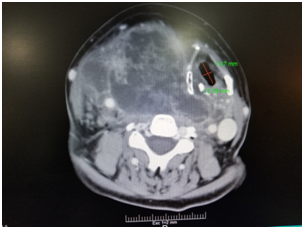

Preoperative tests revealed no nutritional deficiencies. At the first physical examination, the patient is shown with a volume increase in the neck with a neck circumference of 66 centimeters, the largest limited oral opening, a chest x-ray is performed presenting retrosternal goitre with displacement and narrowness of the airway to the left. Therefore, computed tomography is taken, revealing narrowness of the larynx of 7.4x17.09 mm corroborated in the reconstruction of the airway (Figure 2–5), so it was scheduled by general surgery for a thyroidectomy plus tracheostomy.

Figure 2 Imaging depicting tracheal deviation.

Figure 3 Imaging depicting tracheal deviation and compression.

Figure 4 Imaging depicting tracheal deviation.

Figure 5 CT scan with reconstruction of the airway.